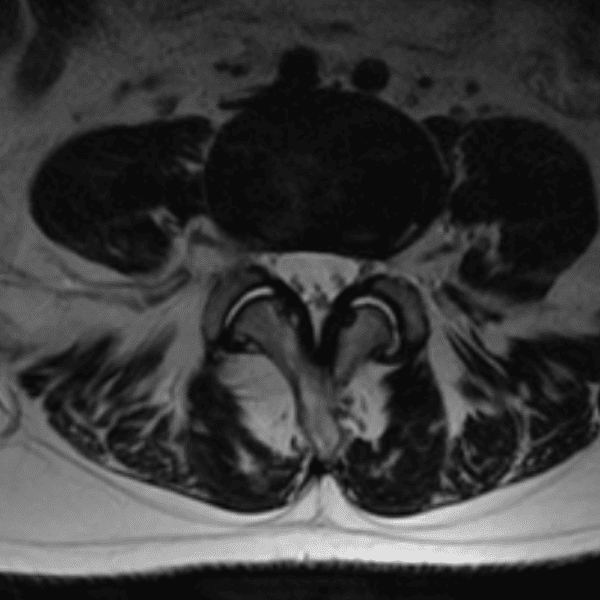

Simulates call by including subtle or difficult cases and some normals.

35 cases